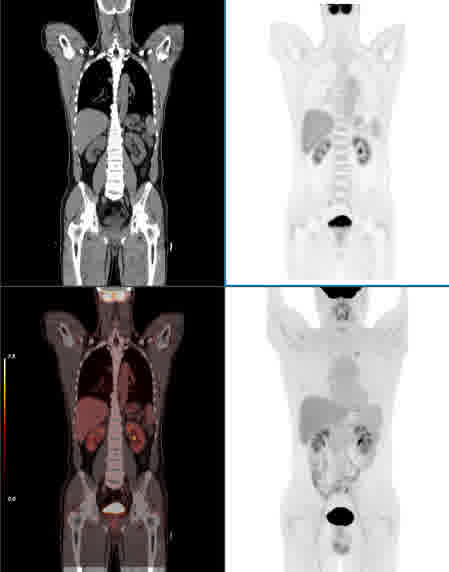

全数据校正

TOF偏差校正

散射校正

基于全链条原始采样数据进行全数字PET信号与图像校正,实现全流程算法智能优化。

CT PET 融合 MIP 无校正 校正后 无校正 校正后 真值图像 传统基于图像的散射校正方法 新型基于能量的散射校正方法 FOV外的高活度射源